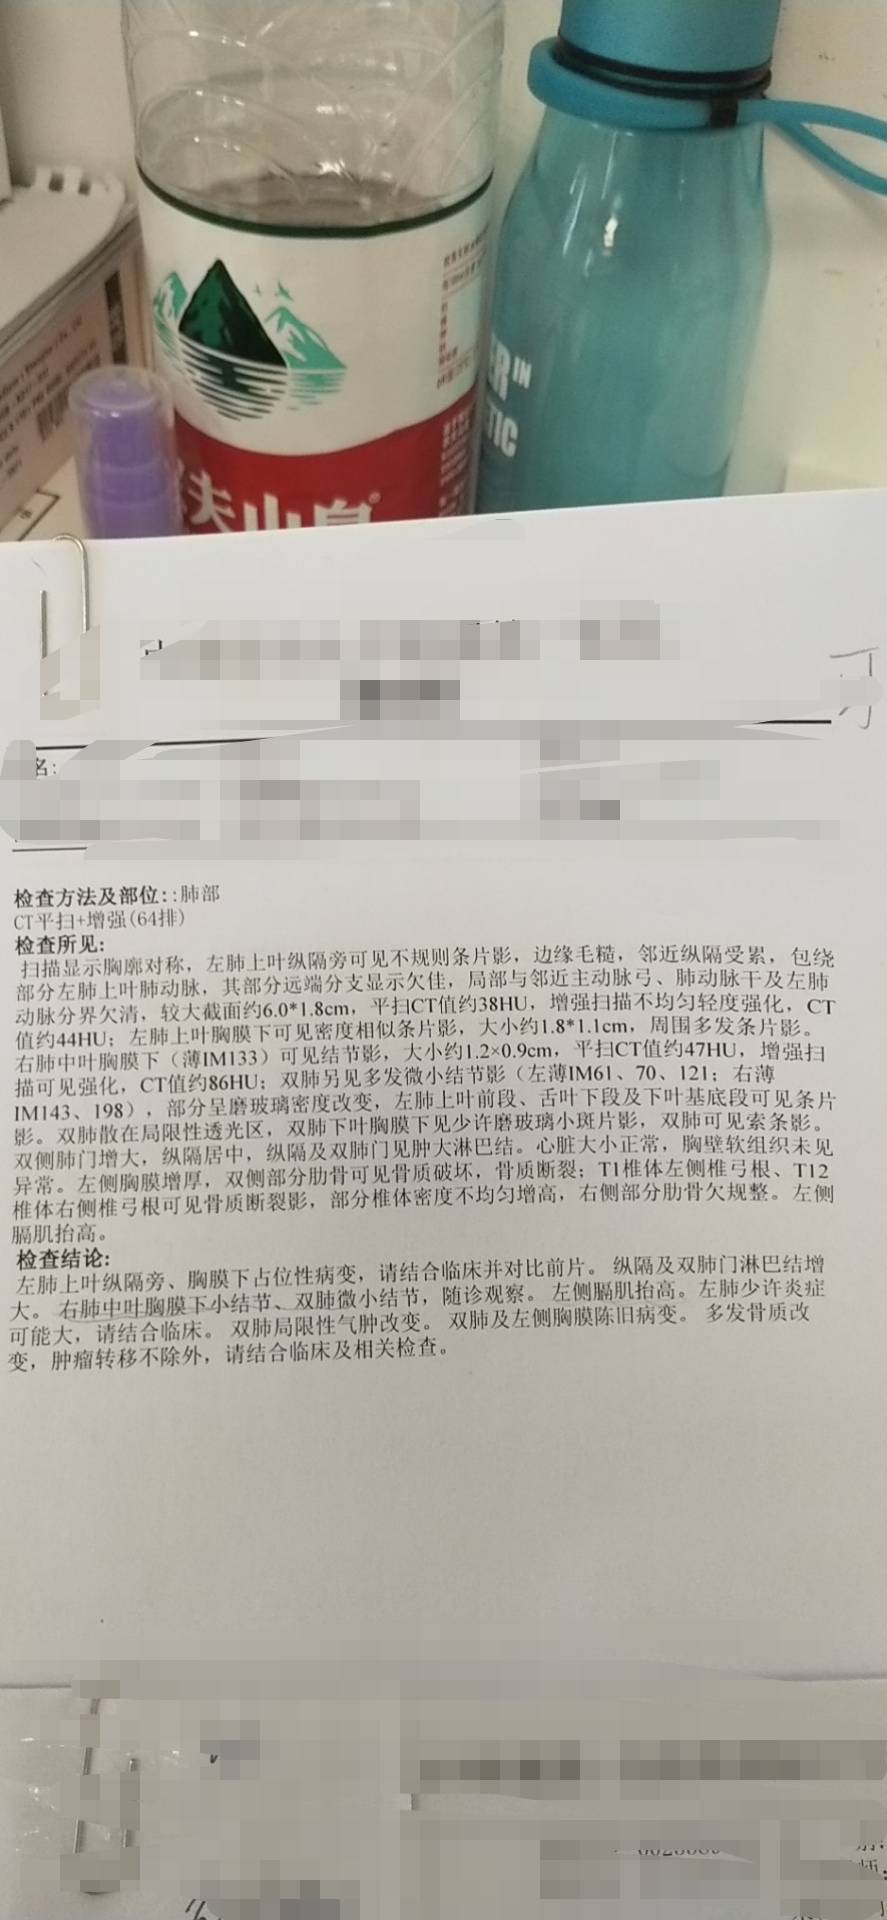

4化后肺CT结果: